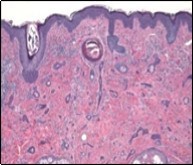

Lesions are generally superficial and infrequently invade lower dermis. Tendency for peri-neural or intra-neural infiltration, cogitated in adjunctive cutaneous carcinomas, is exceptional in desmoplastic trichoepithelioma. Nevertheless, desmoplastic trichoepithelioma can be exemplified as a component of particularly desmoplastic, cutaneous carcinomas demonstrating foci of peri-neural involvement 4, 5. Figure 1, Figure 2, Figure 3, Figure 4, Figure 5, Figure 6, Figure 7, Figure 8.

Figure 2.Desmoplastic trichoepithelioma delineating cords and nests of basaloid cells, few horn cysts and a circumscribing fibrotic stroma 9.